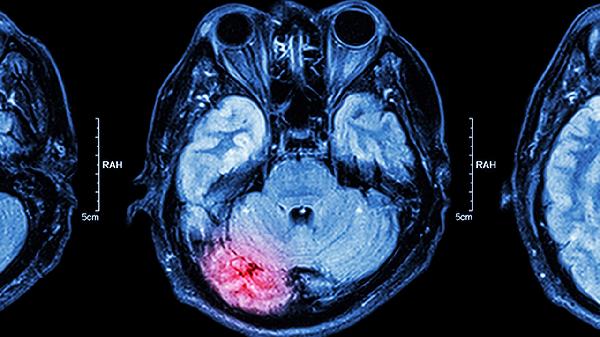

大脑肿瘤可以治好吗

大脑肿瘤是可以治疗的,但治疗效果受到肿瘤类型、位置、大小及患者整体健康状况等多种因素的影响,如果怀疑自己或家人患有大脑肿瘤,请尽早就医。 大脑肿瘤分为良性和恶性两大类。良性肿瘤通常生长较慢,边界清晰

早期脑肿瘤可以治愈吗 如何根除早期脑肿瘤

早期脑肿瘤有可能治愈,具体与肿瘤类型、位置及治疗时机有关。根除方法主要有手术切除、放射治疗、化学治疗、靶向治疗、免疫治疗等。建议尽早就医评估,制定个体化方案。1、手术切除 手术是早期脑肿瘤首选治疗方

脑肿瘤术后能活多长时间

脑肿瘤术后的生存期取决于肿瘤类型、分期、手术效果及术后治疗等多种因素,良性肿瘤患者通常预后良好,恶性肿瘤患者的生存期差异较大,需结合个体情况评估。通过规范治疗和积极康复,可以延长生存期并提高生活质量。